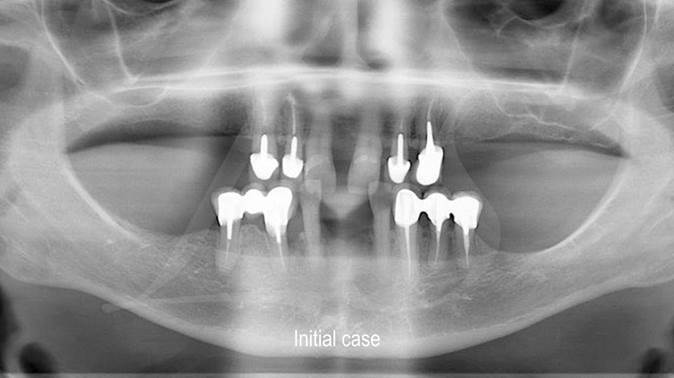

Clinical case: Full-arch implant treatment with immediate loading & extraction implantation

- Courtesy of Dr. Laurent Sers, France -

AnyRidge, R2GATE, guided surgery, Dr. Laurent Sers, immediate loading, maxilla

AnyRidge implant system, R2GATE, Digital prosthesis